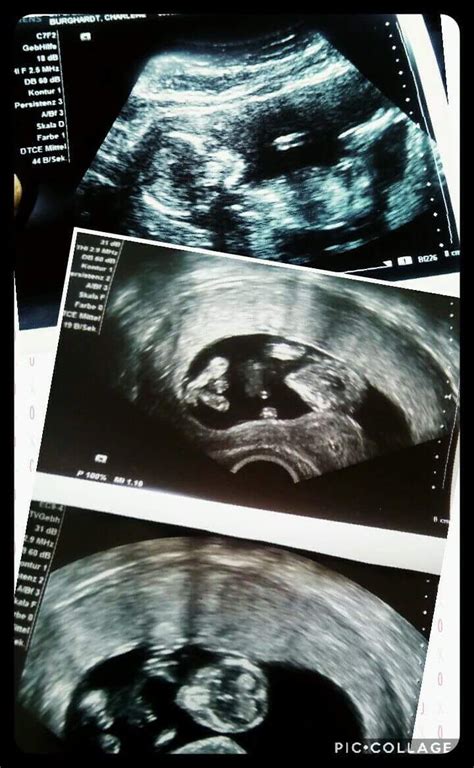

Ultraschalluntersuchung (nackentransparenz) zur erkennung von chromosomenanomalien wie trisomie 21 (down syndrom), trisomie 18 (edwards syndrom), trisomie 13 (pätau syndrom) in der 12. Von hebamme nadine beermann zuletzt aktualisiert am 8. Die mutter in der 13. Wäre schon noch etwas früh. Kann man geschlecht in 13+3 ssw bei pränataldiagnostik sehen?????

Hab viel gelesen das man bei der nackenfaltenmessung meist das geschlecht besser erkennt und meist sieht man schon ab der 13. Mit einem guten ultraschallgerät und wenn der fötus in der richtigen position liegt, könnte sogar das geschlecht schon erkannt werden.